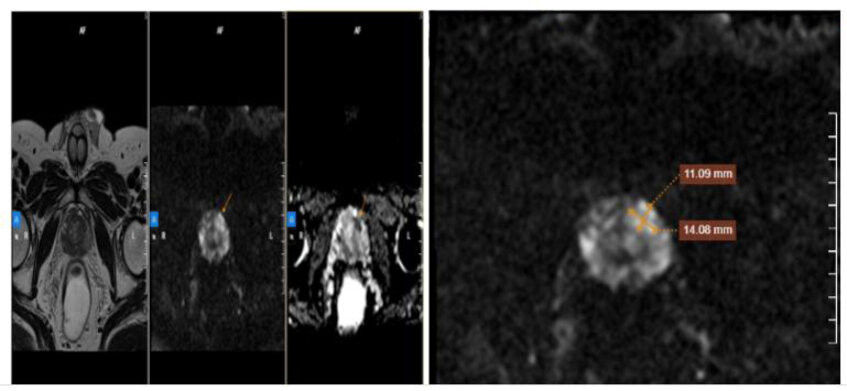

Hình ảnh chụp cộng hưởng từ tuyến tiền liệt (MRI) cho thấy vùng ngoại vi của tuyến tiền liệt có tổn thương nghi ngờ ác tính (PIRADS 4). Ông Phan ngay lập tức được cho làm sinh thiết tuyến tiền liệt dưới hướng dẫn siêu âm qua ngả trực tràng, kết quả sinh thiết không nằm ngoài dự đoán, người bệnh bị ung thư tuyến tiền liệt ở cả hai thùy trái và phải, với điểm Gleason 7 (3+4).